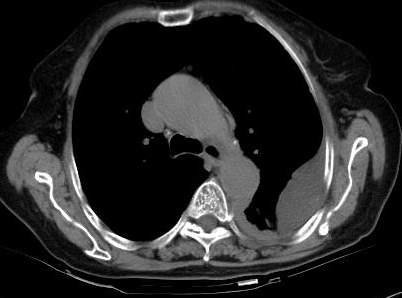

标题: CT0563:病历讨论,胸膜间皮瘤? [打印本页]

标题: CT0563:病历讨论,胸膜间皮瘤?

请上传纵隔窗。目前还是支技包裹性积液(明显梭形),即使是间皮瘤并积液也少梭形的。

从图片看,包裹性积液好象更合理,梭形,ct值3-5hu(在哪看到的?);胸膜间皮瘤如此规则,不多见。

左侧背部胸膜肥厚,伴包裹性积液,不考虑间皮瘤.

同意以上各位的高见,首先考虑包裹性积液,1.胸膜间皮瘤积液量一般较大,以游离性积液更为常见,2.可以看到增厚的胸膜结节